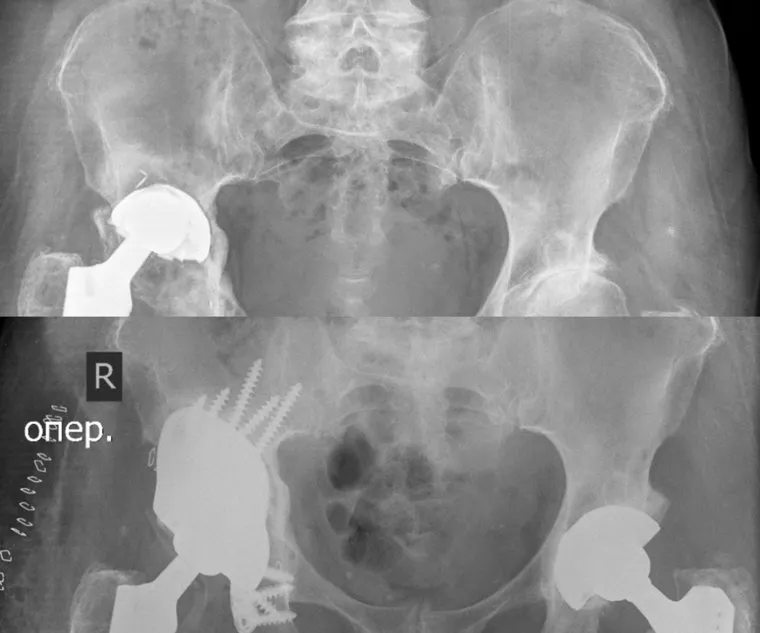

Курганские врачи центра им. Илизарова совместно с инженерами из Новосибирска провели сложную операцию пациентке из Забайкальского края с большим дефектом таза. Женщине установили титановый имплантат. Об этом сообщает пресс-служба медучреждения.

«72-летняя женщина попала в медцентре с нестабильностью эндопротеза. В результате длительно нерешаемой проблемы, у пациента сформировался большой дефект тазовой кости в области вертлужной впадины. Партнерство с инженерами из Новосибирска позволило расширить технологические подходы к данной проблеме. Из титана был напечатан индивидуальный имплантат сложной формы для будущего эндопротеза тазобедренного сустава», — написано в группе «НМИЦ ТО им. акад. Г.А. Илизарова Минздрава РФ» в соцсети «ВКонтакте». Операция длилась четыре часа.

Дорогостоящая операция для женщины была сделана бесплатно в рамках клинической апробации. Это уже вторая пациентка из Забайкальского края, которой врачи центра им. Илизарова установили индивидуальный тазовый компонент с использованием 3D-технологий.